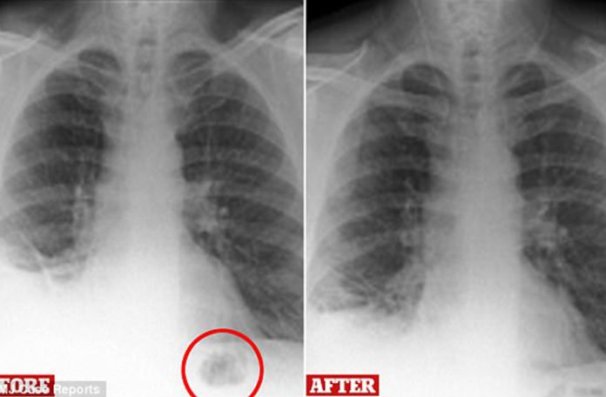

Muškarcu su pluća poslikali rendgenom te je uočena mrlja na plućnom krilu što su odmah povezali s činjenicom da je riječ o dugogodišnjem pušaču. Odmah su posumnjali na tumor. Upućen je na daljnje pretrage te su otkrili da nije riječ o tumoru – u plućnom krilu našli su plastični čunj iz Playmobil seta za djecu kojeg je muškarac progutao prije 40-ak godina.

Čunjić je odstranjen, a muškarac je zatim otkrio kako se kao dječak često igrao sa setom saobraćajnih znakova koji je sadržavao čunjiće. Dobio ga je za 7. rođendan.